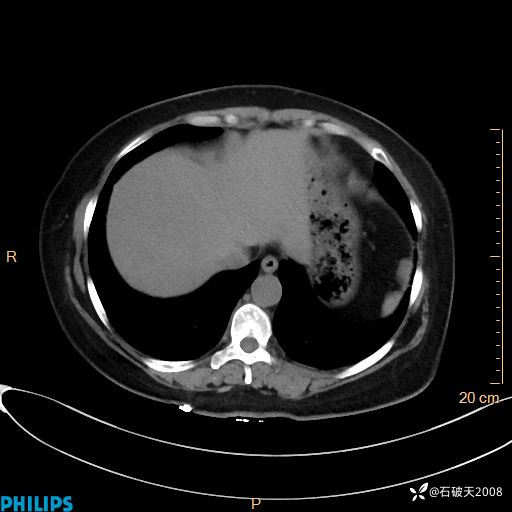

肺结节病?纵膈型肺癌?淋巴瘤?有点意思,欢迎围观

女 52岁 主 诉:咳嗽10余天,咳痰2天。

现病史:10余天前无明显诱因出现咳嗽,呈阵发性干咳,伴咽喉部发痒,无咽痛,无咳痰,无鼻塞、流涕、打喷嚏,无发热、畏寒、寒颤,无头痛、头晕,无胸闷、胸痛,无反酸、烧心,无腹痛、腹泻,无尿频、尿急,无皮疹等,在当地诊所求治,给予口服药物治疗(具体不详),病情无好转。遂在当地社区卫生服务中心开具口服药物治疗(具体不详),疗效欠佳。2天前出现咳痰,在我院门诊求治,行胸部CT提示肺部感染,建议住院,患者要求口服药物治疗,目前仍咳嗽、咳白色粘痰,白天量多,夜间自觉喉部喘鸣音,遂再次来院就诊,以“肺部感染”为诊断收入院。发病以来,神志清,精神可,饮食可,夜间睡眠差,大小便正常,近期体重无明显变化。

静脉期